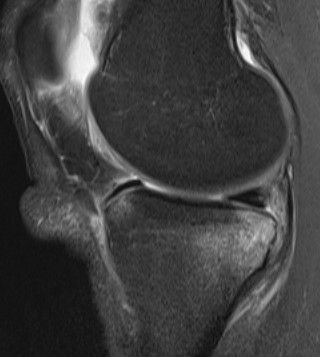

Normal ACL on MRI

Characteristics

- straight structure

- able to see continuity of fibres from tibial to femur

- parallel to intercondylar notch

- no anterior subluxation of the tibia

- normal to have some increased signal due to adipose and synovial tissue